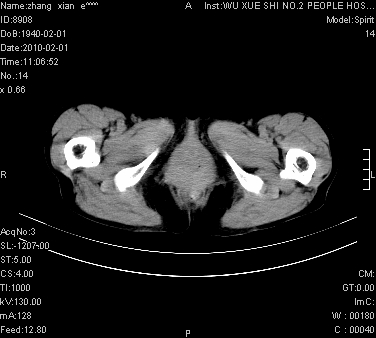

标题: CT24434:70岁 女 腹胀,腹水原因待查 [打印本页]

标题: CT24434:70岁 女 腹胀,腹水原因待查

大量腹水,脾脏囊性占位,子宫颈占位,右侧腹股沟淋巴结肿大,建议+c,先查妇科。

腹盆腔大量积液,子宫增大,子宫颈增大外形不规则,内见低密度影,膀胱后壁显示不清,右腹股沟肿大淋巴结,脾脏囊性占位,子宫颈占位,子宫颈癌?建议增强。

腹盆腔大量积液,子宫增大,子宫颈增大外形不规则,内见低密度影,膀胱后壁显示不清,右腹股沟肿大淋巴结,脾脏囊性占位,子宫颈占位,子宫颈癌?建议增强。支持!